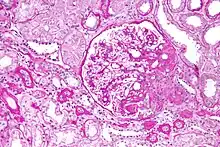

Micrograph of the collapsing variant of FSGS (collapsing glomerulopathy). A collapsed glomerulus is seen at the top, right-of-centre. PAS stain. Kidney biopsy.

Five mutually exclusive variants of focal segmental glomerulosclerosis may be distinguished by the pathologic findings seen on renal biopsy:[34]

1. Collapsing variant

2. Glomerular tip lesion variant

3. Cellular variant

4. Perihilar variant

5. Not otherwise specified (NOS) variant.

Recognition of these variants may have prognostic value in individuals with primary focal segmental glomerulosclerosis. The collapsing variant is associated with higher rate of progression to end-stage renal disease, whereas the glomerular tip lesion variant has a low rate of progression to end-stage renal disease in most patients.[9] The cellular variant shows similar clinical presentation to collapsing and glomerular tip variant but has intermediate outcomes between the other two variants.[9]